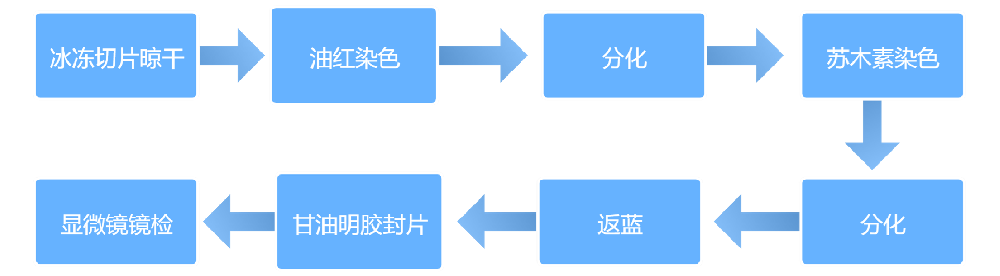

实验流程